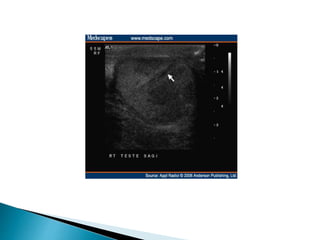

 In the acute stage ultrasound may be normal or

demonstrate a swollen testicle with patchy or

diffuse hypoechogenicity .

 Doppler ultrasound with sensitivity of 85% in the

diagnosis of torsion reduced vascularity

(absence or poor colour flow, reduced peak

systolic velocities) compared with the unaffected

side.

 Torsion maybe complete or incomplete and spontaneous torsion and detorsion may occur  The degree of torsion determines the severity of the ischemia  In the acute stage ultrasound may be normal or demonstrate a swollen testicle with patchy or diffuse hypoechogenicity .  The epididymis may also become swollen and echo-poor.  There may be a reactive hydrocele and the overlying scrotal skin may be thickened and oedematous.

 Doppler ultrasoundwith sensitivity of 85% in the diagnosis of torsion reduced vascularity (absence or poor colour flow, reduced peak systolic velocities) compared with the unaffected side.  Given the importance of operating within a few hours of the onset of symptoms  Neither the performance nor interpretation of an ultrasound examination should delay surgical treatment.  If there is doubt the urologist should operate on clinical grounds